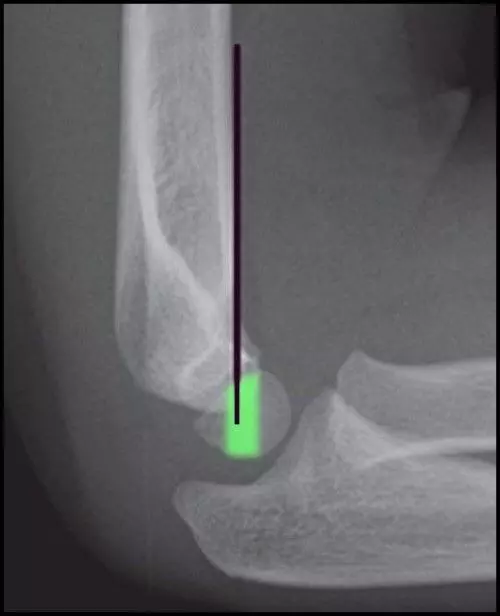

Diagram - An X-Ray of a normal humerus. The black line (the anterior humeral line) should normally pass through the middle third of the capitulum (highlighted green), but if it doesn't, it indicates that there is a supracondylar humerus fracture

Creative commons source by Tracy Kilborn, Halvani Moodley, Stewart Mears and Mikael Häggström [CC BY-SA 4.0 (https://creativecommons.org/licenses/by-sa/4.0)]